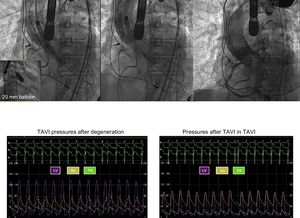

The patient was a 71-year-old man with severe aortic stenosis and coronary artery disease diagnosed in 2008. At the time, he had intermediate surgical risk but nevertheless refused surgery as a therapeutic option. Percutaneous revascularization was therefore undertaken, with implantation of a 26-mm CoreValve aortic prosthesis. The patient was free of symptoms with stable gradients until 2016, when the gradients started to increase, and symptoms reappeared in November 2017. Computed tomography angiography and ultrasound study showed signs of prosthesis degeneration, leaflet calcification (Figure 1A), leaflet thickening (Figures 1B and C) and increased gradient (Figure 1C). When the patient was aged 81 years, a 26-mm CoreValve Evolute Pro was successfully implanted in the existing prosthesis. Figure 2 (TAVI, transcatheter aortic valve implantation) shows details of the procedure and the hemodynamic changes in the aorta (Ao), left ventricle (LV), and pulmonary artery (PA). It has been shown that surgical biological prostheses that have undergone degeneration can be successfully treated with percutaneous aortic prostheses. However, there is no information on percutaneous prosthesis degeneration after 10 years, given that survival in recipients of such prostheses is lower and so such events are rare. To our knowledge, this is the first published case of a self-expanding prosthesis with degeneration 10 years after implantation that was treated with another percutaneous prosthesis. It demonstrates that this is a feasible and safe approach. If outcome is confirmed, this case could help to extend the indication for percutaneous prostheses to patients with intermediate risk.